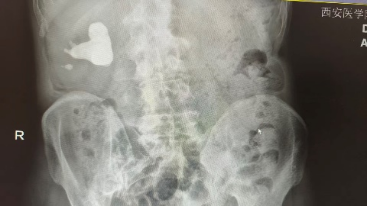

李先生(化名)50余岁,在一次常规体检中被告知“右肾结石”。他没有腰痛、血尿,也无发热等不适,原以为只是“小问题”。在西安医学院第一附属医院泌尿外科门诊,副主任医师宋益挺详细了解病史、结合影像资料后,建议完善泌尿系CT检查。然而,检查结果却让人意外:右肾重度积水,肾盂系统内充满铸型结石,最大直径约6cm。

这是典型的肾铸型结石(Staghorn Calculus),结石形态如“鹿角”,几乎填满整个肾集合系统。若继续发展,肾组织将逐渐萎缩,甚至导致肾功能永久丧失。